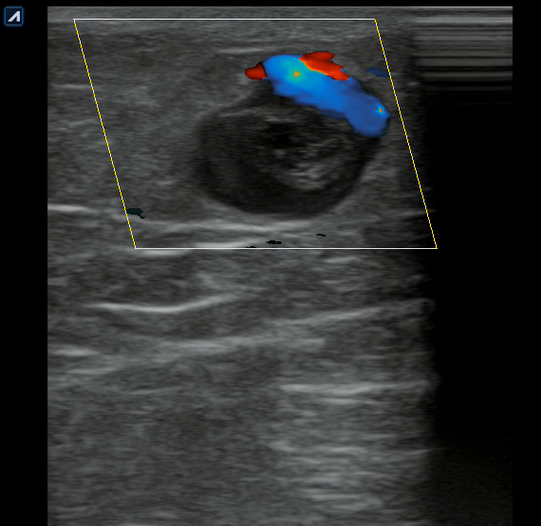

Se realiza ecografía clínica en consulta donde observamos a nivel inguinal adecuada compresibilidad de vena femoral y relleno con Doppler color. Cayado de safena libre y compresible. A 7 cm de distancia del cayado se aprecia, en territorio de safena, dilatación no compresible de la misma, contenido intraluminal ligeramente ecogénico y ausencia de Doppler color compatible con trombosis venosa superficial de 19 cm de distancia. Se estudia recorrido donde se observa en zona de dilataciones varicosas material ecogénico con ausencia de paso de Doppler alternando con zonas de paso parcial. En tercio distal de muslo comienza a desaparecer. Vena femoral profunda, poplítea y perforantes sin datos de trombosis.